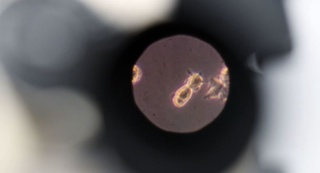

Япон тадқиқотчилари ниқоблар коронавирусни тўсиб қўйишини кўрсатиб берди, аммо у ҳам мукаммал эмас

Япониялик тадқиқотчилар ниқоблар ҳаводаги коронавирус зарраларидан ҳимоя қила олишини, аммо ҳатто профессионал даражадаги қопламалар ҳам юқтириш хавфини тўлиқ бартараф эта олмаслиг...